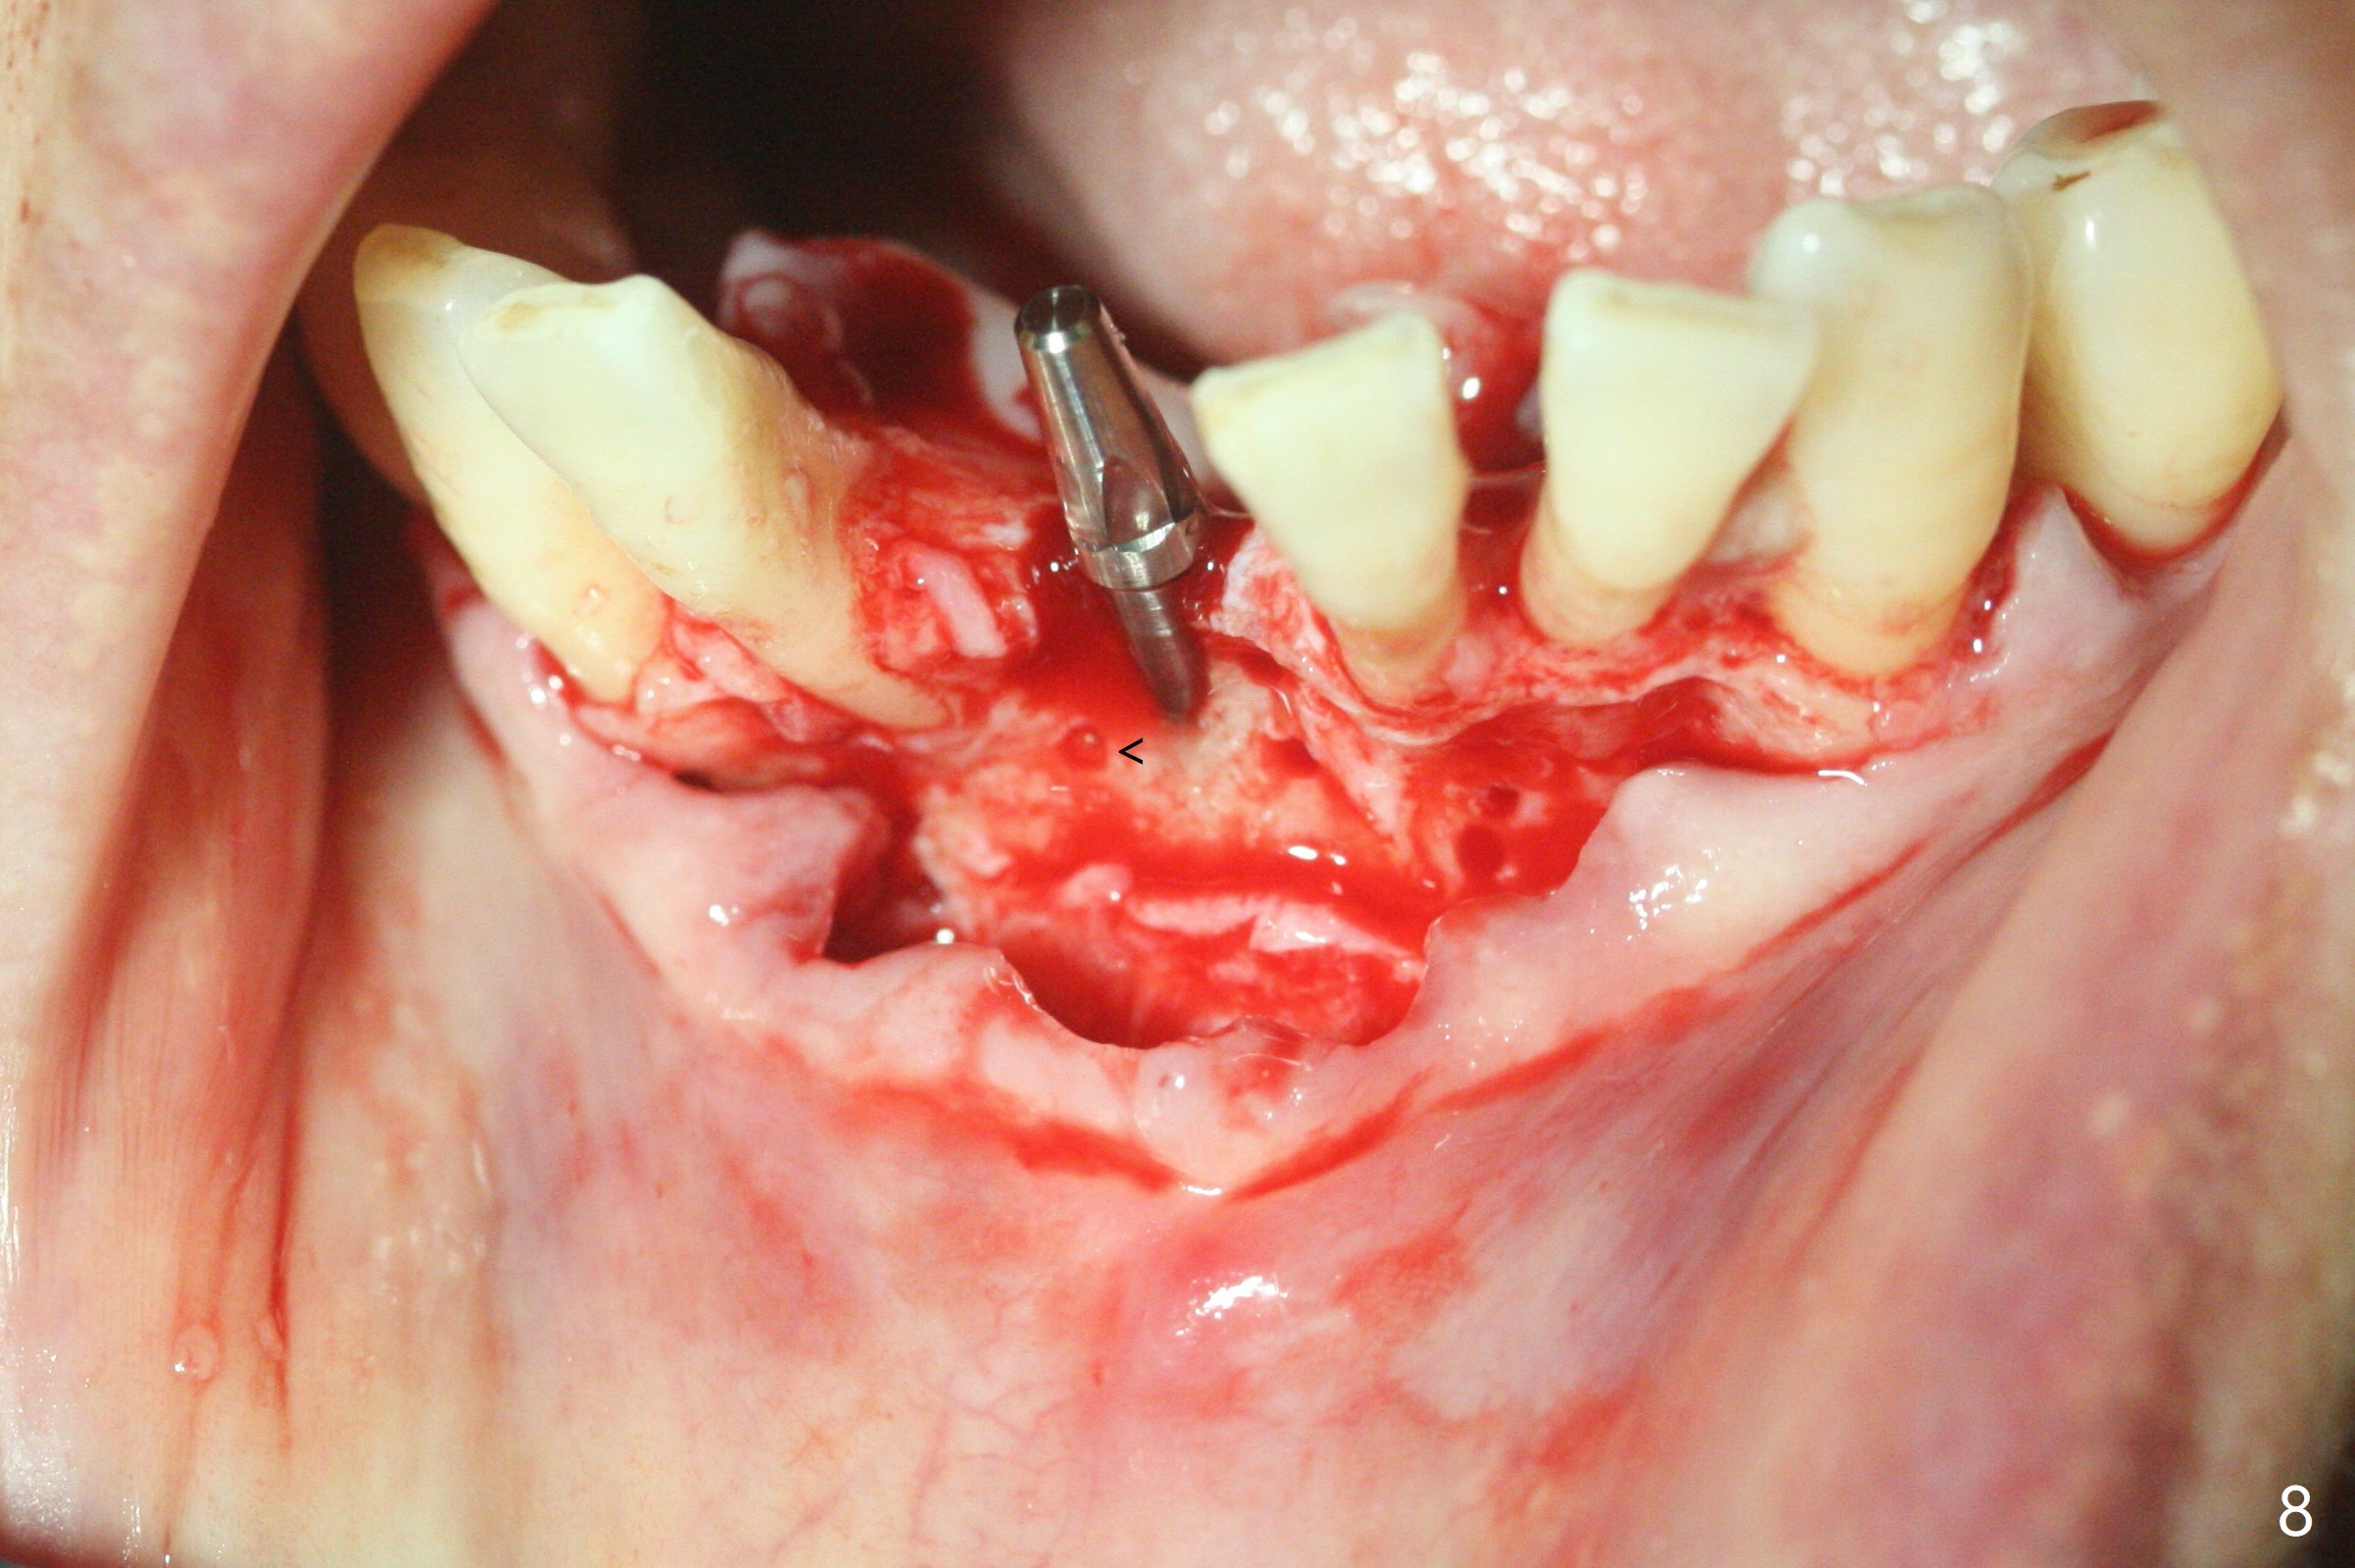

56岁女十分恐惧治疗,缺失右下1,其余切牙由于骨质吸收颊侧移位(图一:1,2),但是她不愿意拔除,同意右下1种植,牙周骨手术,植骨;植体整合后作为支抗,矫正移位下门牙。为了防止忘记舌侧瓣分离,先做舌侧切口(图二),然后颊侧瓣松弛分离(图三),包括使用前牙隧道刀(图四)切断颊侧骨膜,松弛到颊侧瓣能向舌侧牵拉3-4毫米(图五),舌侧瓣骨膜下广泛,深部分离(好像不能切断骨膜,图六),放置导板,磨平狭窄的牙槽嵴(图七:O(osteotomy)),植入2.5x12(4)毫米一段式植体(图八:故意舌侧植入,以便以后矫正),在颊侧骨板打多个出血洞(图八:箭头),然后把在平的器皿上形成的粘性骨板(sticky bone,图九),放置于植体和移位切牙周围(图十),接着使用消毒过的橡皮障punch(图十一(纸头相当于PRF膜;事先给助手示范))在三个PRF膜(图十二)打洞,套在植体和门牙上(图十三: 箭头),防止膜(图十四)和骨块(图十五,十六:*)移位,最后还必须使用最原始方法牙周敷料保护伤口(图十七)。术后9天,舌侧牙周敷料脱落,伤口稍微裂开(图十八)。术后18天撤除敷料,伤口裂开处有新鲜肉芽组织生长(图十九(*:下面是填入的骨粉,将是增宽的牙槽嵴(如果你是乐观主义者)),二十)。病人十分感激我们帮助她度过难关。她的确有sleep apnea,否定tongue thrust。术后三个月植体周围没有明显骨质吸收(图二十一至二十三),左下1,2轻度反合(图二十四),植体周围软组织健康(图二十五),5-5安置矫正器(图二十六,二十七,12 niti)。一周后下切牙向舌侧移动(图二十八),左下1,2反合纠正(图二十九)。再一周变化不大(图三十),植牙圈有些松动,两周后将重做临时牙冠,槽往舌侧移动。结果病人提前回来,植牙槽舌侧移位。一周后右下2不适(图三十一),尝试近中牵引(图三十二)。